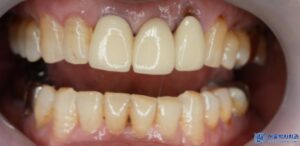

이러한 장점 덕분에 환자분도

완성된 크라운의 색상과 모양, 착용감 등

모두 만족스럽다고 하셨습니다.